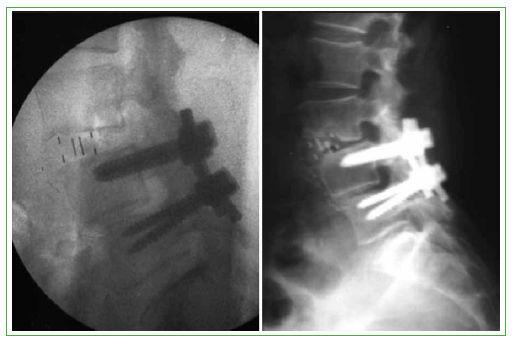

Entre los cuatro pacientes que sufrieron una complicación mayor, dos no fueron sometidos a ninguna cirugía de revisión, pero uno de ellos quedó con dolor neuropático crónico intercostal, se trató de un nivel L1-L2 en donde se resecó parte de la costilla para poder acceder al espacio, y el otro caso fue una escoliosis del adulto en la que se realizó un acceso a los espacios L2-L3 y L3-L4 (el ápice de la curva), y el paciente quedó con una disestesia en la cara anterior de muslo, que continuaba al ano de la cirugía. El tercer paciente con una complicación mayor tuvo una lesión de la arteria segmentaria en el espacio L3-L4, la cual se pudo ligar, con la ayuda de un cirujano vascular, por la misma incisión y fue necesario realizar una vía posterior, alterando la estrategia quirúrgica original. En el posoperatorio inmediato del cuarto paciente, se observó una fractura longitudinal del cuerpo de L3, se le colocó una caja en L2-L3 que quedó muy anterior y una caja en el nivel inmediato inferior (L3-L4) colocada más posterior, esto generó una debilidad de ambos platillos vertebrales del cuerpo de L3, por donde se produjo el trazo fracturario, que se solucionó mediante una fijación posterior complementaria (Figura 1).

Figura 1.

Paciente con fractura del cuerpo de L3.

Otra complicación infrecuente es la fractura del cuerpo vertebral. En el estudio de Brier-Jones y cols.,14 se reportaron cuatro pacientes con fracturas intraoperatorias del cuerpo vertebral, todas por ruptura del platillo vertebral. Los autores lo atribuyen a la colocación de una placa lateral con tornillos muy cerca del platillo vertebral, esto llevaría a que se altere el hueso trabecular por debajo de este, debilitándolo y generando una sobrecarga que conduciría a la caja a fracturar el platillo. También otros autores asociaron la fractura del cuerpo a la colocación de una placa lateral de sostén, como muestran Kepler y cols.15 Nosotros tuvimos un solo caso, en el que no colocamos placa lateral, pero sí fijación pedicular posterior complementaria. Creemos que se debió a una violación del platillo inferior del disco superior al colocar la primera caja y luego a la debilitación del platillo superior del disco inferior al cuerpo de L3 al colocar la segunda caja, provocando el trazo de fractura longitudinal. Este tipo de complicaciones se podría evitar, como ya mencionamos, con el manejo cuidadoso en la preparación del platillo, procurando no debilitarlo. También al implantar las cajas intersomática se deberían utilizar las valvas protectoras de los platillos y no distraer excesivamente el espacio con implantes muy grandes, sobre todo en los pacientes con osteoporosis importante. La migración lateral de la caja es una rara complicación del abordaje lateral. En la bibliografía, solo encontramos el reporte de un caso con una migración lateral de la caja, a pesar de la fijación posterior.16 El cuadro era sintomático y fue necesaria una revisión quirúrgica para solucionarlo. Towers y Kurtom17 refieren un solo caso de migración lateral, pero sin fijación posterior y asintomática, que no requirió revisión. Esto último es similar a nuestro único caso de migración lateral en una fusión lateral L3-L4, pero con fijación posterior, el paciente no tenía síntomas y no hubo necesidad de una nueva cirugía.